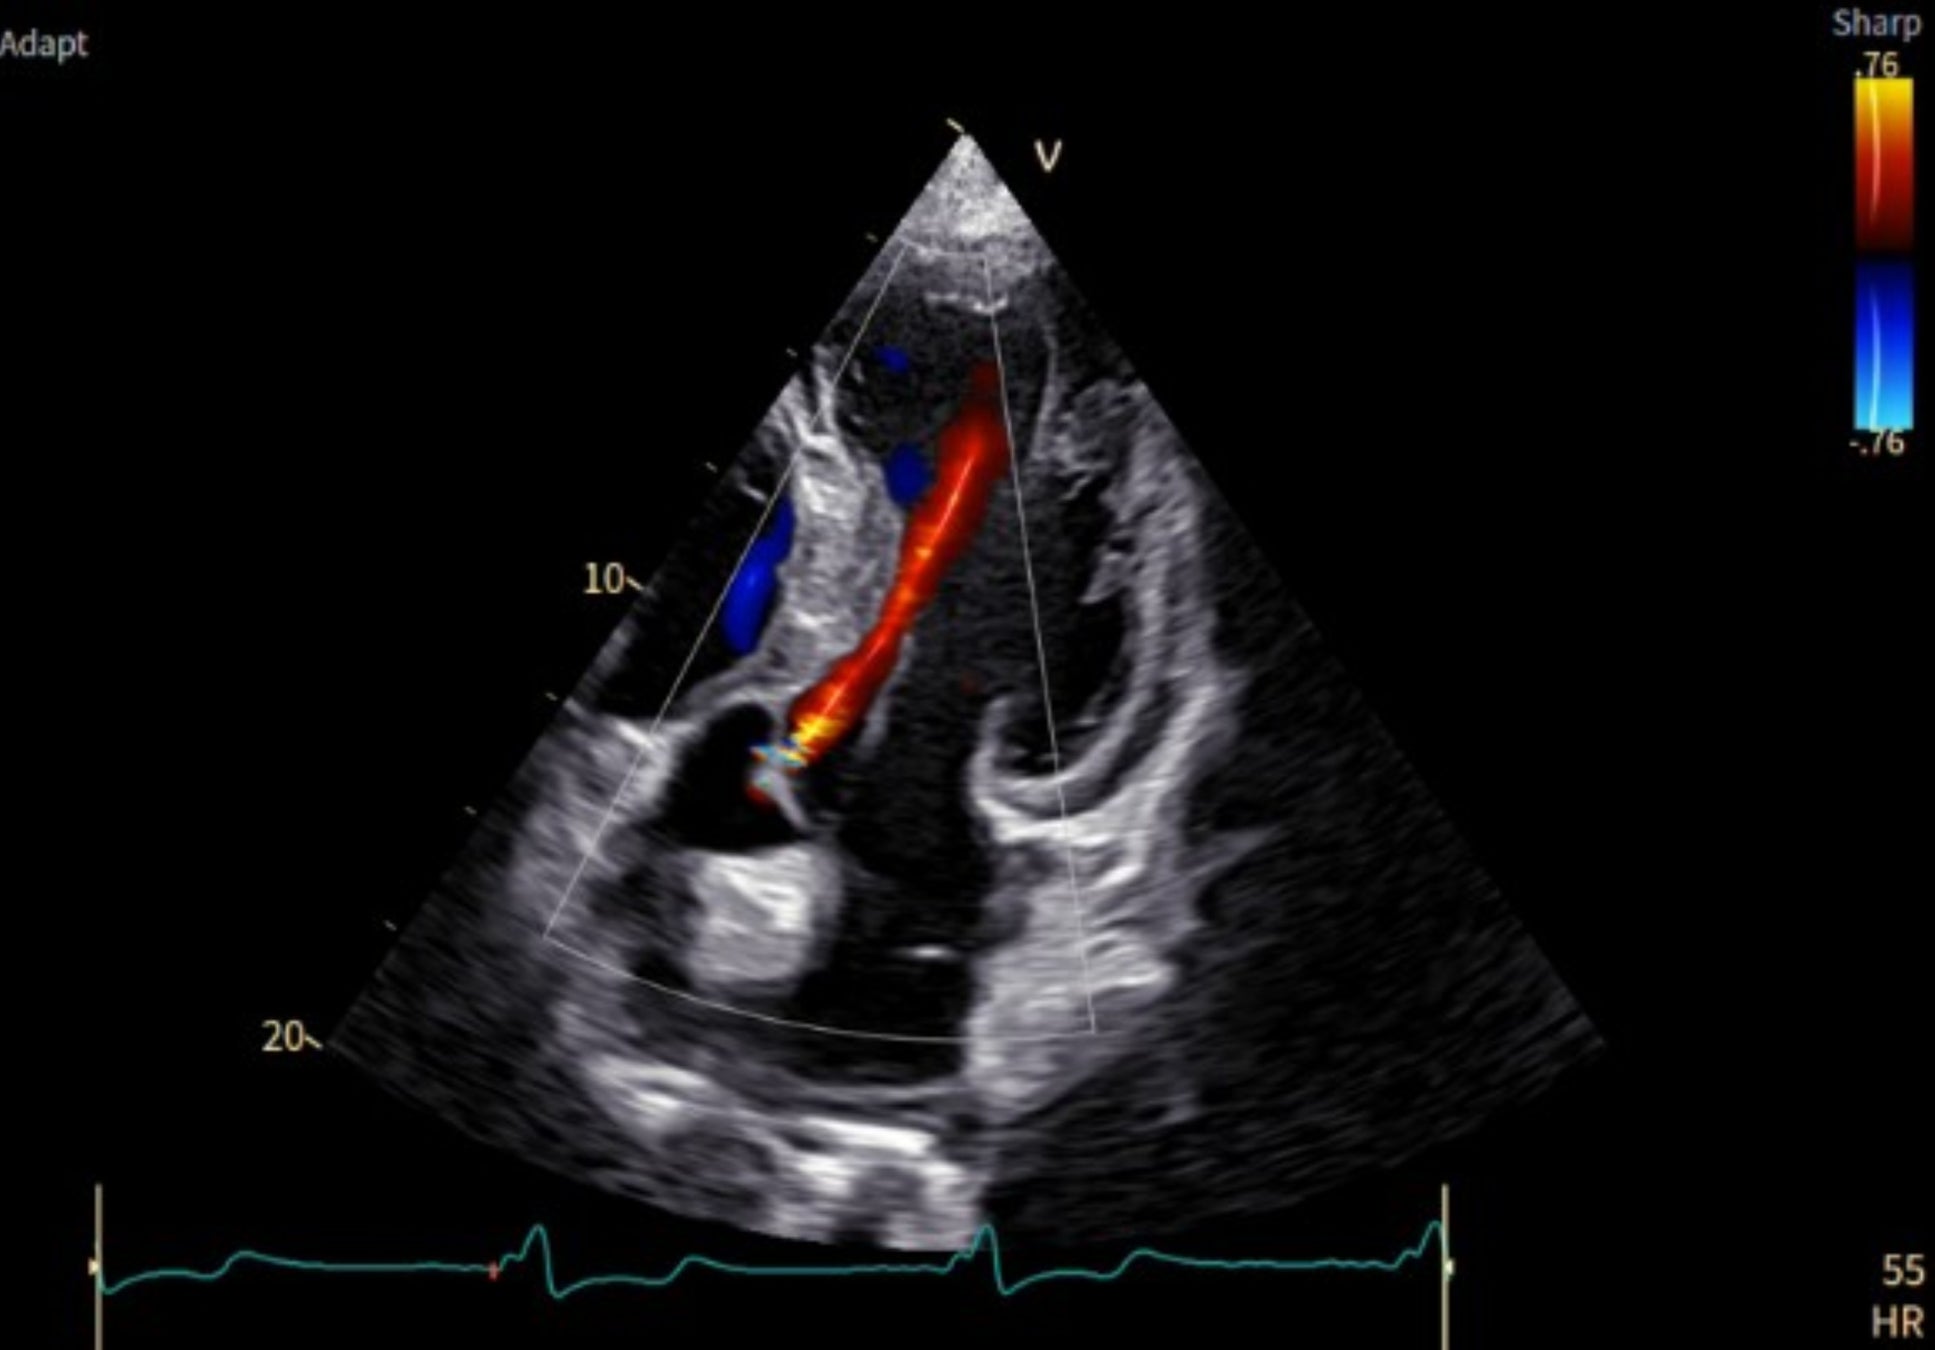

「Vivid Pioneer」は、これまで検査者が手作業で行っていた血流解析をAIが自動で行い、短時間で安定した測定プロセスを提供します。また、心臓の主要な部位(左心室と左心房)の動きや形を三次元で自動分析し、検査者間の標準化を支援します。そのほか、次世代の画像エンジン機能により、細部の見やすさ(空間分解能)や色の見やすさ(カラー感度)が向上し、より高精度な心臓の立体画像を描出します。